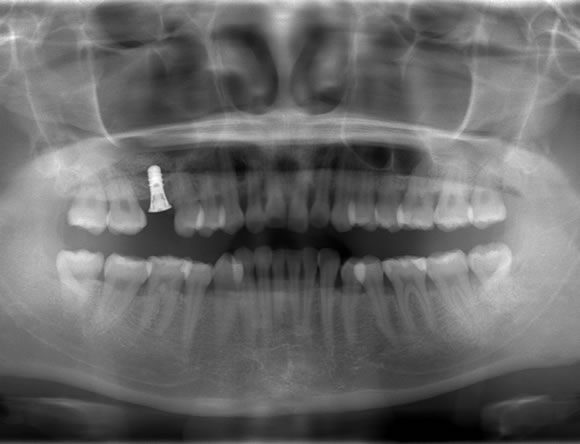

正中過剰埋伏歯 症例

正中過剰埋伏歯の症例です。鼻腔底直下にあるので、静脈内鎮静を使い無痛抜歯で対応しました。抜歯が怖い方はご相談下さい。

料金は保険適用で約10,000円の治療費用です。